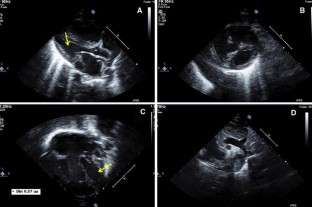

Fig. 1